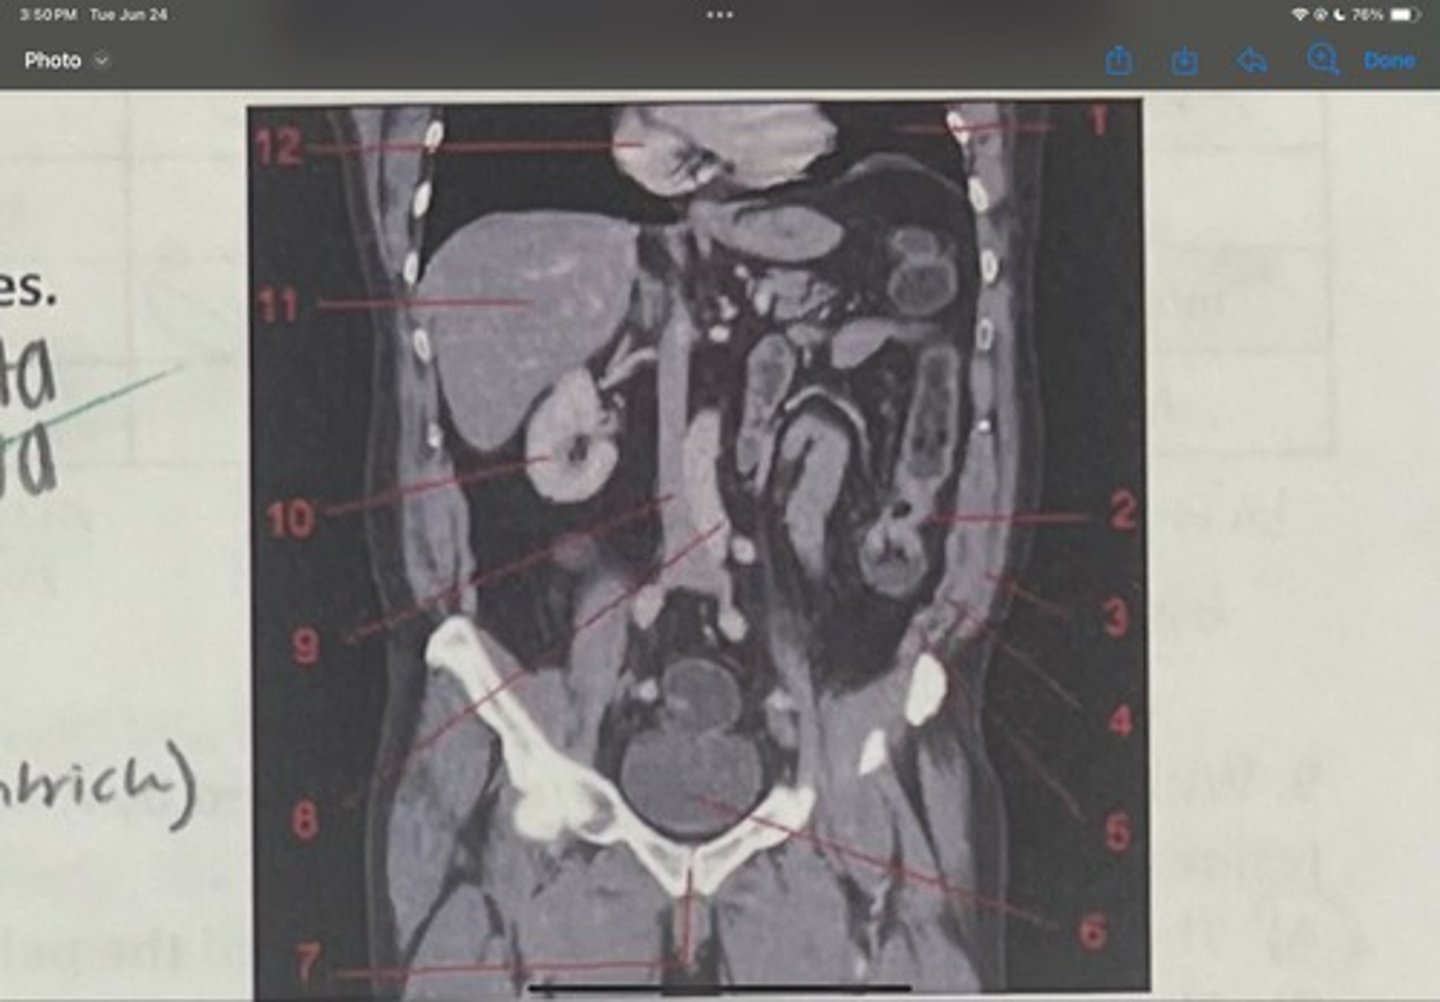

What is 1

Descending colon

What is 2

External oblique

What is 3

Internal obliques

What is 4

Transversus abdominis

What is 5

Bladder

What is 6

Pubic sysmphysis

What is 7

Abdominal aorta

What is 8

Inferior vena cava

What is 9

Right kidney

What is 10

Liver

What is 11

Heart (right ventricle)

What is 12

Subcostal nerve (T12)